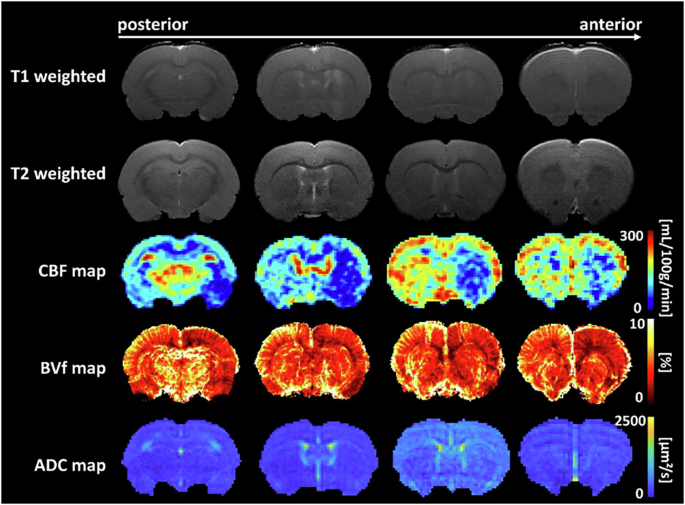

Other sequences

In addition to T2w, T2*w and SWI previously described, several recent publications have assessed the safety of FUS-mediated BBB opening procedures using more sophisticated MR sequences, such as diffusion-weighted imaging (DWI)20,29,31,38, DTI41,109, arterial spin labeling (ASL)12,29,41, or MR angiography (MRA)84. First applied by Tu et al. in 2020109, DTI was combined with chemical exchange saturation transfer (CEST) imaging to investigate morphological and metabolic changes following FUS-mediated BBB opening in rats at 9.4 T. These sequences were acquired one day, two weeks, and six weeks after sonication to assess the effects of multiple weekly FUS procedures. They observed morphological changes in rats receiving multiple weekly FUS + MB treatments, indicated by hyperintense voxels in DTI images. In addition to DTI, Rigollet and colleagues measured cerebral blood flow (CBF) using a pulsed arterial spin labeling (pCASL) sequence (derived from ASL)41. They studied the dynamics of CBF after sonication in rats and noted a decrease in CBF immediately following FUS + MB procedures, Fig. 6. However, this vasoconstriction was transient, with CBF returning to baseline 90 minutes after sonication. A similar decrease in CBF in the sonicated region was observed by the same group29. To complement their MR protocol, they applied DWI to measure the apparent diffusion coefficient (ADC) to identify hyperintense or hypointense voxels and detect any microhemorrhages caused by the procedure. Additionally, the vascular anatomy of the primate brain was imaged using a 3D time-of-flight sequence at 3 T after FUS + MB procedures84. In this work, the authors did not detect any vascular damage in MRA images.

Representative MRI images (T1w, T2w, CBF map, blood volume fraction (BVf) map, ADC map) obtained from one animal after FUS-induced BBB disruption. Figure adapted with permission from ref. 41.

In conclusion, while T2w, T2*w, and SWI remain the primary sequences used to ensure the safety of FUS-induced BBB opening procedures, recent studies utilizing functional sequences to measure CBF or ADC have demonstrated their value in studying both the immediate and long-term vascular impacts of single or repeated sonication procedures.